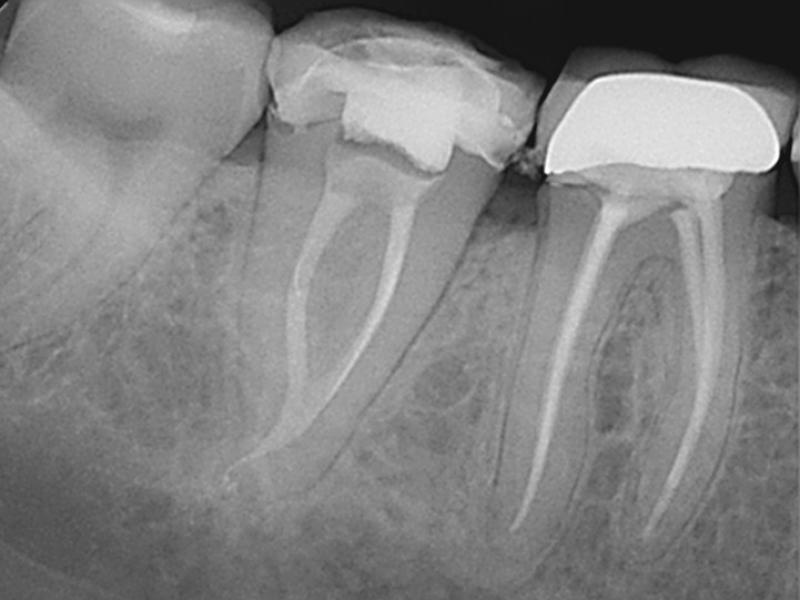

Pre-Op